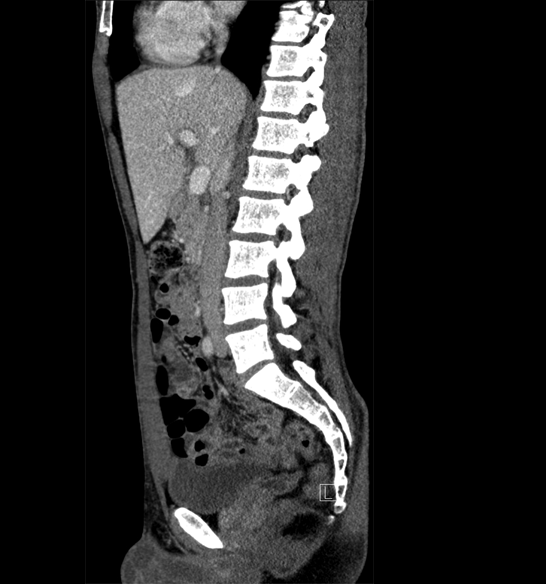

Body

Covers abdominal CT anatomy.